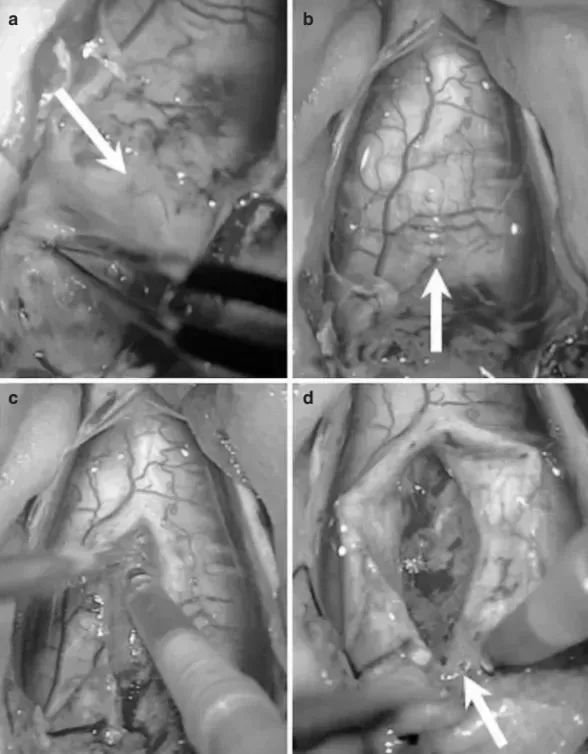

手术台上,年幼的米亚被小心安置为俯卧位。巴特朗菲教授选择了远外侧手术入路。行远外侧入路为米亚切除了肿瘤,通过枕下开颅术、 C1 椎板切除术及 C2 和 C3 椎板成形术进行充分的肿瘤暴露术中磁共振协助确认肿瘤切除情况 (d)。

教授采用远外侧入路切除肿瘤,术中细致暴露肿瘤,控制出血、保护延髓正常组织